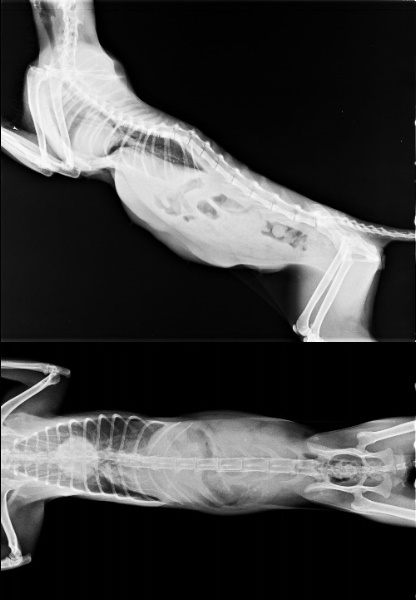

主題: 圓仔一家五口住院 申請者姓名: 臺北市支持流浪貓絕育計劃協會 花色: 申請日期: 2014-03-14 18:25:02 申請者部落格: 申請者臉書網址: 所在縣市/合作醫院: 台北市/極光動物醫院 治療費用: 21650元 需求人數: 23人 已結案 (2014-03-24 18:11:34) 報名人員: ERic YU(已付款)、Mandy Yeh(已付款)、Vicky(已付款)、Daniel Tsai(已付款)、Ch Huang(已付款)、Claire Huang(已付款)、paula chen x4(已付款)、ONE(已付款)、Yupei Hsu(已付款)、00(已付款)、mee(已付款)、lofxbaytu(已付款)、小黃(已付款)、Sunny Chen(已付款)、Ou Han x2(已付款)、Shi Jie Chen(已付款)、Chris Chen(已付款)、Andrea Ouli x2(已付款)、 候補人員: 動物病情說明: 這筆費用為一月19日-1月23日圓仔一家五口住院費用申請,

為第一筆醫助

由於院方較忙碌

只先行結算第一階段住院費

第二階段1月24日-3月份住院費將於院方四月份帳務處理後

再行招募

目前只剩下貓媽媽仍在與頑強病毒奮戰,

四隻小圓仔已於住院數天後相繼往生,

這是今年的第一件憾事。